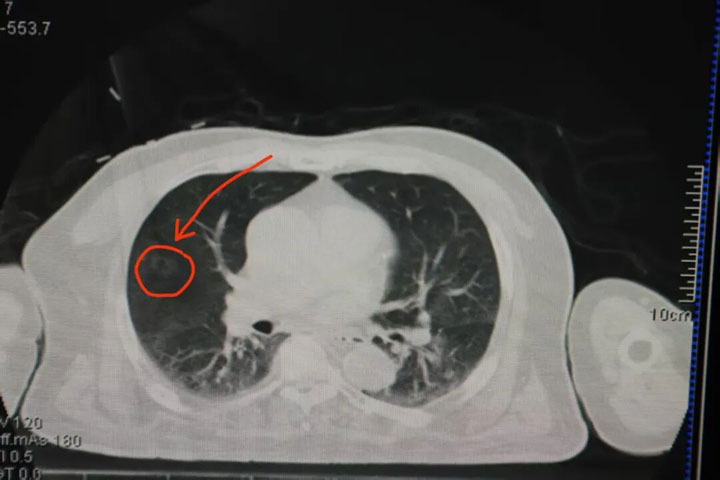

下图可见:术前CT下结节大小及位置